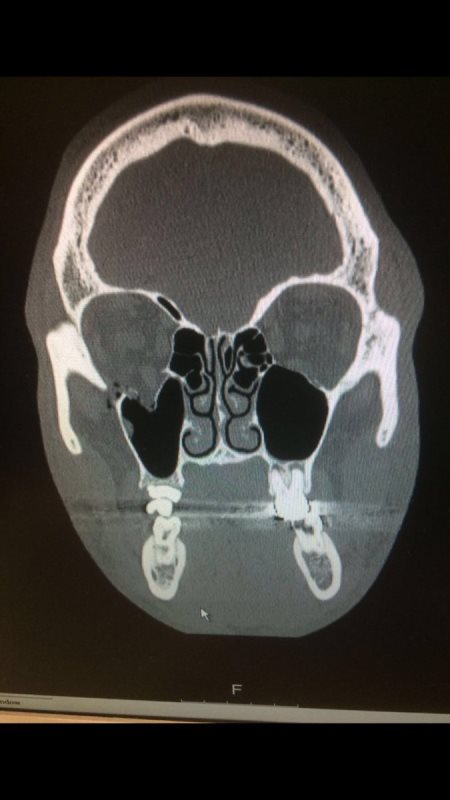

«Операция по сломанной глазнице пройдет в понедельник в Шеффилде. Доминик Ингл вывел меня из боя, чтобы избежать большего вреда здоровью, который мог случиться», — написал в Твиттере Брук, прикрепив рентгеновский снимок.